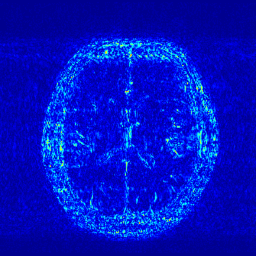

We illustrate with reconstructions for three CS-MRI methods: TLMRI (transform learning MRI) [25], PANO (patch-based nonlocal operator) [23] and GBRWT (graph-based redundant wavelet transform) [14]. The PANO and GBRWT models achieve impressive reconstruction qualities because they use an nonlocal prior and adaptive graph-based wavelet transform to exploit image structures. In TLMRI, the sparsifying transform learning and the reconstruction are performed simultaneously in more efficient way than DLMRI [24]. The three methods represent the state-of-the-art performance in the non-deep CS-MRI models. In Figure 2, we show the reconstructions error for zero-filled (itself a potential reconstruction “algorithm”), TLMRI, PANO and GBRWT on a complexed-valued brain MRI using 30%percent3030\% Cartesian under-sampling. The error display ranges from 0 to 0.2 with normalized data. The parameter setting will be elaborated in the Experiment Section V.

We also consider the deep learning DC-CNN model [26] as the guide module. We also give the reconstruction error in Figure 2. We observe the zero-filled, TLMRI, PANO, GBRWT and DC-CNN models all suffer the structural reconstruction errors, while the DC-CNN model achieves the highest reconstruction quality with minimal errors because of its powerful model capacity. Another advantage of this CNN model is that, once the network is trained, testing is very fast compared with conventional sparse-regularization CS-MRI models. This is because no iterative algorithm needs to be run for optimization during testing since the operations are a simple feed forward function of the input. We compare the reconstruction time of TLMRI, PANO, GBRWT and DC-CNN for testing for Figure 2 in Table I.

Figure 2: The reconstruction error of a brain MRI using zero-filled, TLMRI, PANO, GBRWT and DC-CNN under 1D 30%percent3030\% under-sampling mask.